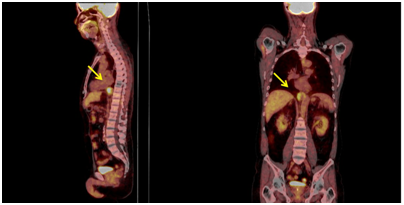

A 59-year-old male who was under surveillance post liver transplant from HCC 4years ago, had elevated alpha fetoprotein (AFP) at 258.3ng/ml and a positron emission tomography–computed tomography (PET-CT) showing an increased uptake lesion of standardized uptake value (SUV) 7.5 at gastro-esophageal junction (Figure 1). Upper endoscopy showed unremarkable esophageal mucosa so EUS was performed showing a homogeneous hypoechoic mass measuring 35x20mm from the 3rd layer of the distal esophageal wall (Figures 2.1 & 2.2) and EUS-FNA was performed. Cytopathology was consistent with metastatic HCC (Figures 3.1 & 3.2). The patient expired 20months later from progressive disease with systematic bacterial infection despite multidisciplinary treatments.

Figure 1 Positron emission tomography (PET) scan showed abnormal uptake of SUV 7.5 at gastroesophageal junction of distal part of the esophagus.